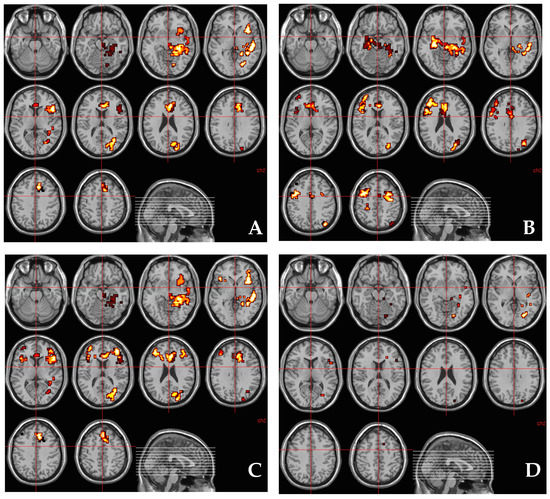

3.3. Regional Brain Response to THC during Fear Processing

3.4. Relationship between AKT1 Genotype (rs1130233) and the Effect of THC on Regional Brain Activation during Fear Processing

3.5. Relationship between Methylation at CpG11–12 Site around AKT1 SNP (rs1130233) and the Effect of THC on Regional Brain Activation during Fear Processing

3.7. Relationship between AKT1 Genotype (rs1130233) and the Effect of THC on Regional Brain Activation during Fear Processing after Covarying for Methylation at CpG11–12 Site